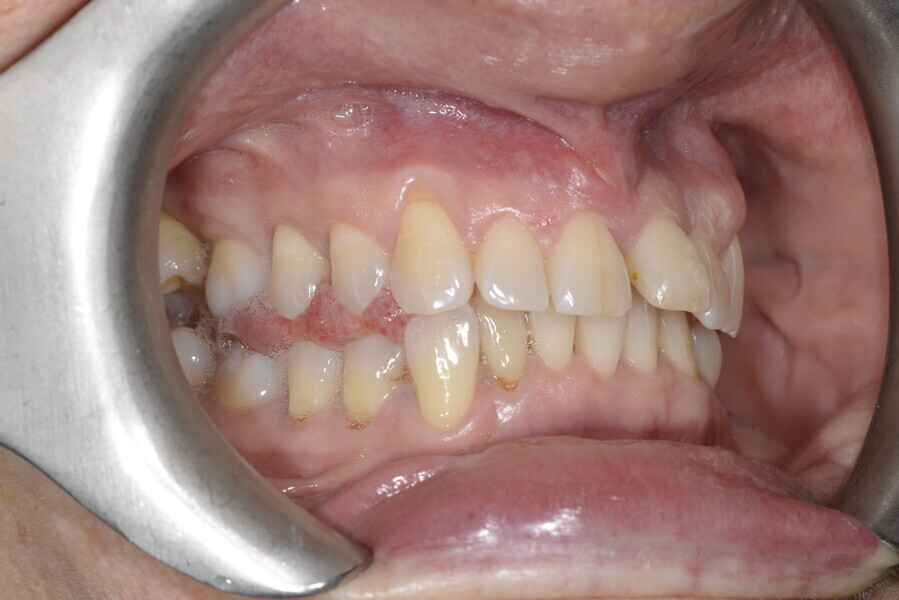

The 58-year-old patient wished to improve his oral aesthetics and function, complaining of mobility of the posterior teeth and wear of the anterior teeth. After data collection, a very complex situation was identified (Figs. 11–13):

1. severe periodontitis with poor prognosis of some teeth;

2. anterior crossbite;

3. severe wear mainly of the anterior teeth and compensatory eruption;38

4. atypical swallowing and lower posture of the tongue at rest;

5. masticatory dysfunction during the mastication test; and

6. no significant signs of temporomandibular disorder.